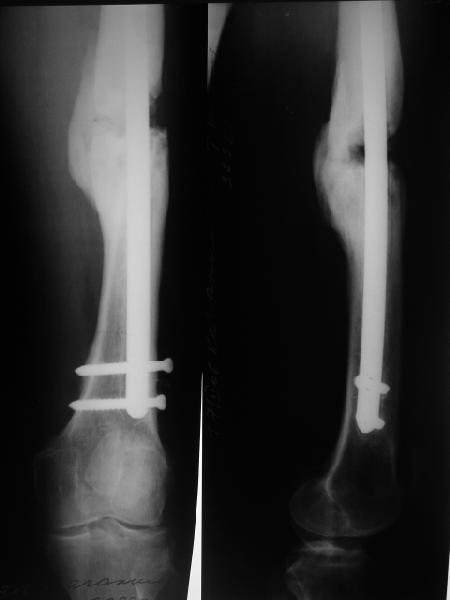

Давайте посмотрим на снимки бедра. В принципе, с наличием "эндопротеза диафиза" в виде мощного интрамедуллярного стержня не надо убиваться с обширными вмешательствами на очаге с кровопотерями, создавать большую площадь контакта, замещать все дефекты. Достаточно образования после дистракции узенького мостика по одной стороне. Со временем он упрочится, стержень в канале будет помогать сохранять длину и ось несколько лет. Даже если не будет смыкания трубок, можно потом стержень отпереть, за счет этого улучшиться контакт. Можно сделать реостеосинтез с рассверливанием стержнем большего диаметра. Важно, что все это время можно нормально пользоваться конечностью.

В приложении снимки бедра - с такой картинкой пациентка ходит, не хромает, работает инженером 3,5 года после операции с первых дней, хотя еще и инсулинозависимый диабет.